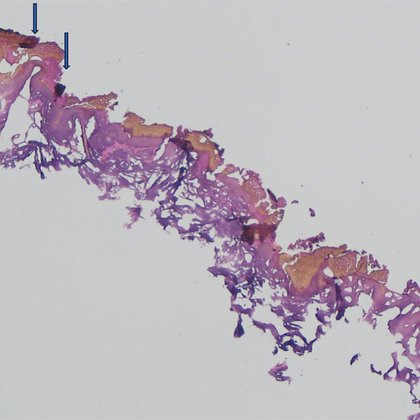

Shaken Baby Syndrome/Abusive Head Injury: The Role of Expert Witness Testimony and a Recent Case Development --- https://t.co/R6RNXQPNNx

link.springer.com

Journal of Bioethical Inquiry - The triad of clinical signs, (extensive bilateral retinal haemorrhages, subdural haematoma, and encephalopathy) is regarded by some expert witnesses as pathognomonic...